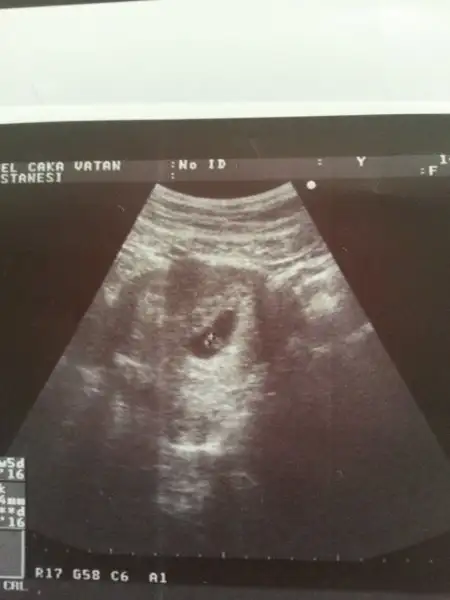

rus cinsiyet takvimini denemedim canım. çünkü eşim neredeyse her yıl kan bağışında bulunur. kan bağışı yapan çiftlerde bu takvim tutmuyormuş. benim de daha 10 hafta dolmadı. ultrason fotoları atayım ama daha çok küçük pek bir şey anlaşılacağını düşünmüyorum ama yine de bakarsanız sevinirimBende çin takvimi, rus cinsiyet takvimi ,biyoloji takvimde denedim kiz diyor.. arti meyve hic sevmem tatli sevmem tuzlu eksi hic birinide sevmem.. netteki butun belirtilere gore alyans yuzuge kadar hepsinde kiz cikiyor...usg resmindede sagda yani ordada kiz.. ki bende tecrubeli bir anne olarak kiz diyorim. 2 hafta sonra gidecem dr. Bakalim o ne diyecek :))))

Eki Görüntüle 1707425 Eki Görüntüle 1707427 birde benim miniğime bakarmısınız hanımlar bu 7+4 günlük ultrason görüntüsü

vayyy terbiyesiz, öyle oyunlar yapmayı da öğrenmiş yani şimdiden, çok işim var benim diyosunuz :)Cnm senin bebek bizimle oynuyor:)ilk resimde solda ikinci resimde sağda o yüZden yorum yapmayacağım.sen 11 12 haftalık fotosunu atarsin ilerde o zaman nubuna bakarım.

Benim tahminim eğer karından bakıldıysa bu bebek kızEki Görüntüle 1707425 Eki Görüntüle 1707427 birde benim miniğime bakarmısınız hanımlar bu 7+4 günlük ultrason görüntüsü

sanki sola daha yakın gibi değilmi ? yani ben oğlum olsun çok istiyorum da :)Benim tahminim eğer karından bakıldıysa bu bebek kız

canım bana da sağa daha yakın gıbı geldi:) rabbim gönlündekini hakkında hayırlı eğlesin inşsanki sola daha yakın gibi değilmi ? yani ben oğlum olsun çok istiyorum da :)